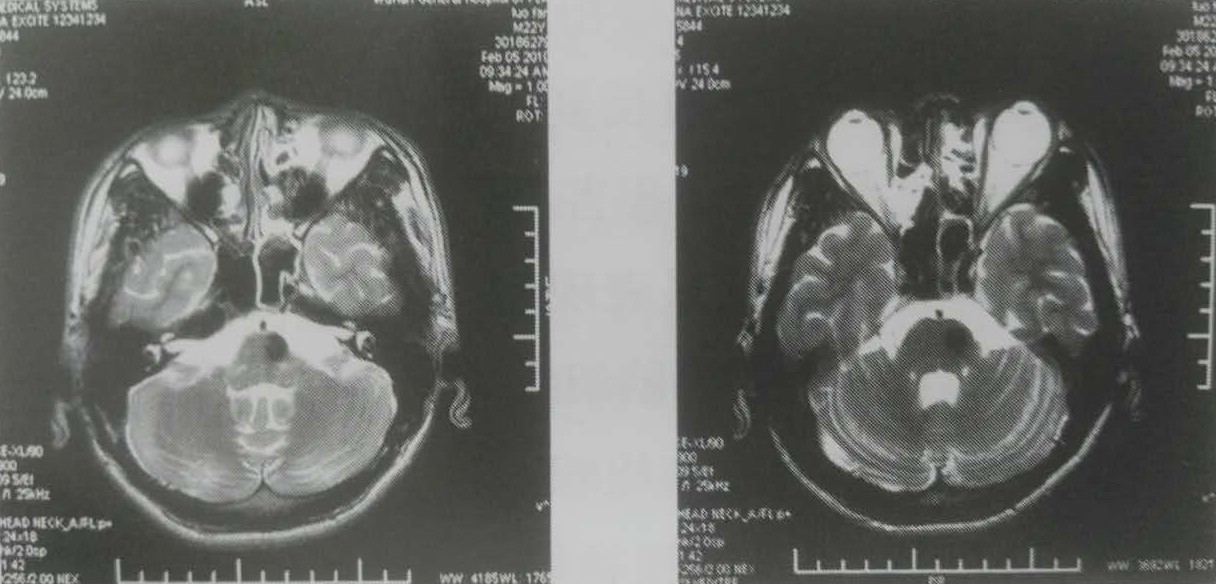

50%的等剂量曲线包饶其边缘,边缘剂量13.5Gy,中心剂量27Gy。2010年2月5日复查症状好转,MRI示T2像原病灶高信号消失,呈低信号改变,无脑水肿,如下图:

伽马刀治疗后18个月复查MRI示原高信号消失